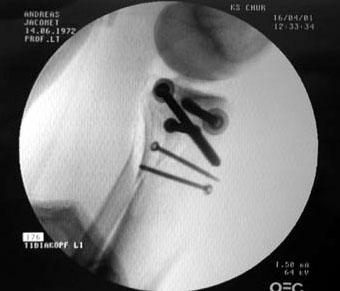

So geht das heutzutage: Kein Gips mehr, dafür vom Anfang an Bewegungsschiene (unter Schmerzen, die ich selbst Monate später noch als Gipfel der Tortur empfand, und das trotz einer geballten Ladung Morphium & Co.).

Belastet werden darf die ganze Konstruktion allerdings nicht, zumindest sechs Wochen lang - Titan und Edelstahl zierten für die nächsten Monate das Schienbein; ans Tageslicht kamen die erstaunlich grossen Schrauben erst im November wieder. Die folgenden Bilder wurden während der Operation gemacht: